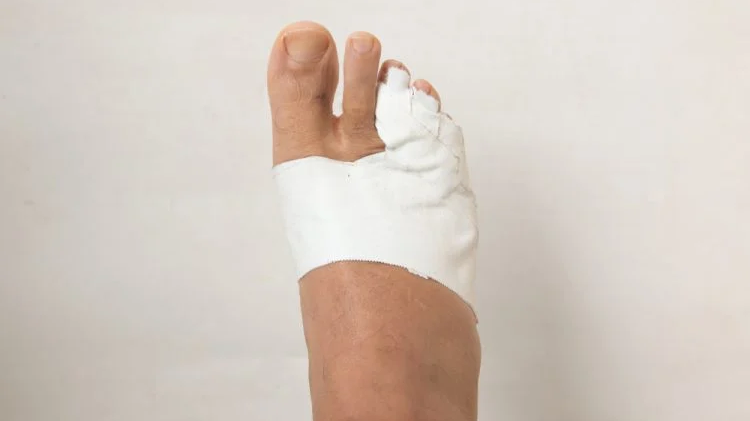

Gãy xương bàn chân số 5, hay còn gọi là gãy xương ngón chân số 5, là một loại chấn thương khá phổ biến, thường cần phải áp dụng phương pháp bó bột để giúp xương hàn lại. Quy trình này là một phần quan trọng trong việc điều trị và phục hồi sau chấn thương. Tuy nhiên, thời gian cần thiết để bó bột tùy thuộc vào nhiều yếu tố. Hãy cùng tìm hiểu gãy xương bàn chân số 5 bó bột bao lâu.

Gãy xương bàn chân số 5 bó bột bao lâu có thể khác nhau tùy thuộc vào nhiều yếu tố như độ nghiêm trọng của chấn thương, tuổi tác, sức khỏe tổng thể và liệu pháp điều trị được áp dụng. Tuy nhiên, trong trường hợp phổ biến, việc bó bột xương bàn chân số 5 thường kéo dài từ 6 đến 8 tuần để cho xương lành lại.

Gãy xương bàn chân số 5 bó bột bao lâu có thể khác nhau tùy thuộc vào nhiều yếu tố như mức độ nghiêm trọng của gãy xương, độ tuổi và sức khỏe tổng quát của bệnh nhân. Thông thường, quá trình phục hồi có thể kéo dài từ vài tuần đến vài tháng. Trong thời gian này, việc tuân thủ các biện pháp điều trị và hướng dẫn của bác sĩ là rất quan trọng để đảm bảo xương nhanh lành và phục hồi hoàn toàn chức năng của bàn chân.